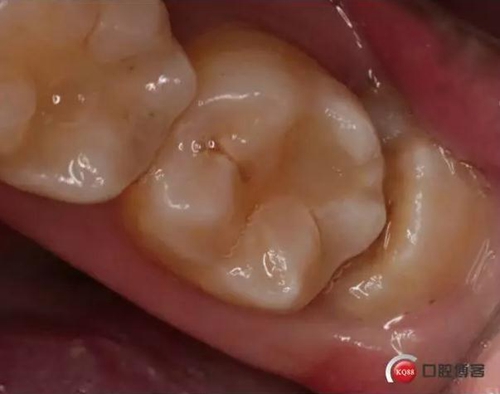

檢查:口內(nèi)可見(jiàn)38未完全萌出,無(wú)松動(dòng),周?chē)例l顏色正常,叩診(—)觸診(—),X線(xiàn)顯示近中阻生,雙根